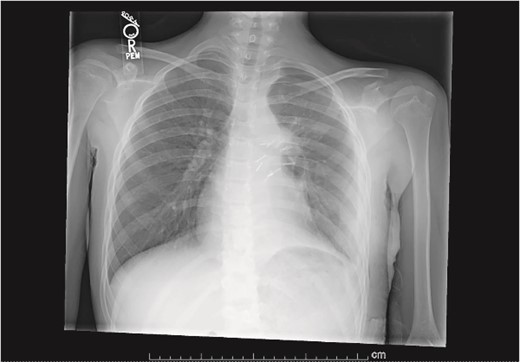

Our patient is a 10-year-old Caucasian female with a history of early adrenarche, ADHD, and COVID-19 and no past surgical history. She presented to the ED with a month-long history of persistent coughing, shortness of breath on exertion and speaking, and left-sided chest pain that began after a diagnosis of mildly symptomatic COVID-19. A physical exam revealed decreased breath sounds on the left, with a left-sided chest protrusion. A plain film and CT demonstrated a normal right lung, with a significant mediastinal shift toward the right, displacement of the heart into the right hemithorax, with complete whiteout of the left hemithorax, and demonstrating a mix of solid and cystic foci, with a round opacification at the left lung base (Figs 1 and 2). The patient underwent an uncomplicated left thoracotomy with excision of two masses, one being 22.5 × 21.0 × 10.5 cm and the other being 13.5 × 11.5 × 6.2 cm. These masses weighed 2394 g in aggregate. The specimens consisted of well-encapsulated tumors attached to the posterior aspect of the chest wall. A regional, positive lymph node measuring 3.0 × 2.2 × 1.0 cm was also resected. Due to the large size of the tumor and the requirement for clean margins, parts of the latissimus dorsi and serratus anterior muscles were also resected. By postoperative day (POD) 0, the left lung had already filled the left hemithorax, and the mediastinal shift had corrected (Fig. 3). The chest tube was removed on POD 5, and a plain film showed continued expansion of the lung to full size and resolving pulmonary edema and atelectasis (Fig. 4). The patient was discharged home on POD 5. The tumor staging was T4N1M0. The tumor was positive for vimentin, CD56, synaptophysin, chromogranin, and NSE. The tumor was negative for pancytokeratin, Cam5.2, EMA, S100, desmin, SMA, SOX10, HMB45, CD117, DOG1, CD99, PR, CD68, WT1, CD30, p53, Alk1, GFAP, and nuclear β-catenin. Next-generation sequencing showed an MGA:NUTM1 fusion, supporting a final diagnosis of high-grade MGA:NUTM1 fusion SCS. Given the size and grading of the tumor, the patient underwent adjuvant CT-RT with ifosfamide, doxorubicin, and proton beam radiotherapy, with supportive doses of MESNA and dexrazoxane for 4.5 months post-operatively. The basis of this treatment is ARST0332 Arm C [6]. Before treatment initiation, the patient underwent an uncomplicated left oophorectomy for reproductive cryopreservation. A PET/CT prior to CT-RT showed hypermetabolic activity in several areas. These included the pleural resection margin, a mediastinal lymph node concerning for metastasis versus postsurgical change, and a left axillary lymph node concerning for metastatic disease. During treatment, the patient contracted human metapneumovirus and rhino/enterovirus, resulting in febrile neutropenia. The patient was successfully treated with blood and platelet transfusions and pegfilgrastim. Upon completion of CT-RT, PET/CT imaging showed no evidence of residual disease, with minimal focal hypermetabolic activity as compared to the previous imaging (Fig. 5).

Plain film on postoperative day 0 depicting the recovery of the left lung post-surgical resection.